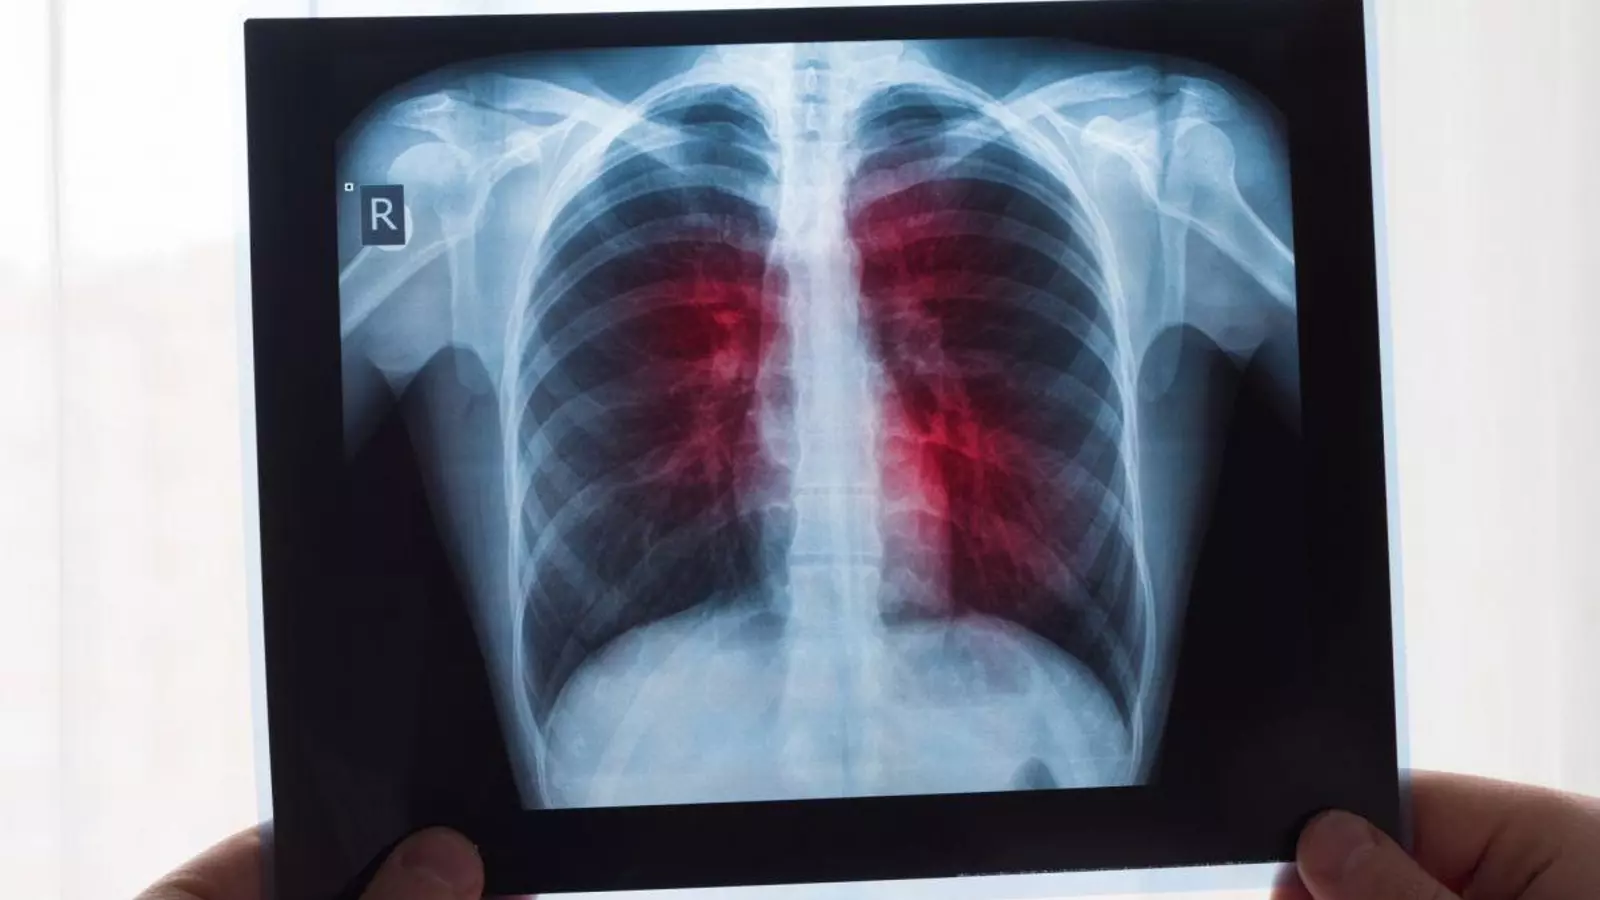

Una herramienta de aprendizaje profundo de inteligencia artificial (IA) que estima el riesgo de malignidad de los nódulos pulmonares logró altas tasas de detección de cáncer, a la vez que redujo significativamente los falsos positivos, según expertos del Centro Médico Universitario Radboud de Nimega, Países Bajos.

El cáncer de pulmón sigue siendo un problema de salud global importante, causando la mayor cantidad de muertes por cáncer en todo el mundo. Se demostró que el cribado de personas de alto riesgo mediante tomografía computarizada de tórax de baja dosis reduce la mortalidad por cáncer de pulmón. Sin embargo, los ensayos de cribado temprano reportaron altas tasas de falsos positivos, lo que conlleva procedimientos de seguimiento innecesarios, mayor ansiedad en los pacientes y mayores costos de atención médica.

Los nódulos pulmonares (pequeños crecimientos redondos u ovalados en los pulmones) son comunes, y determinar cuáles son malignos es un desafío en la detección del cáncer de pulmón.